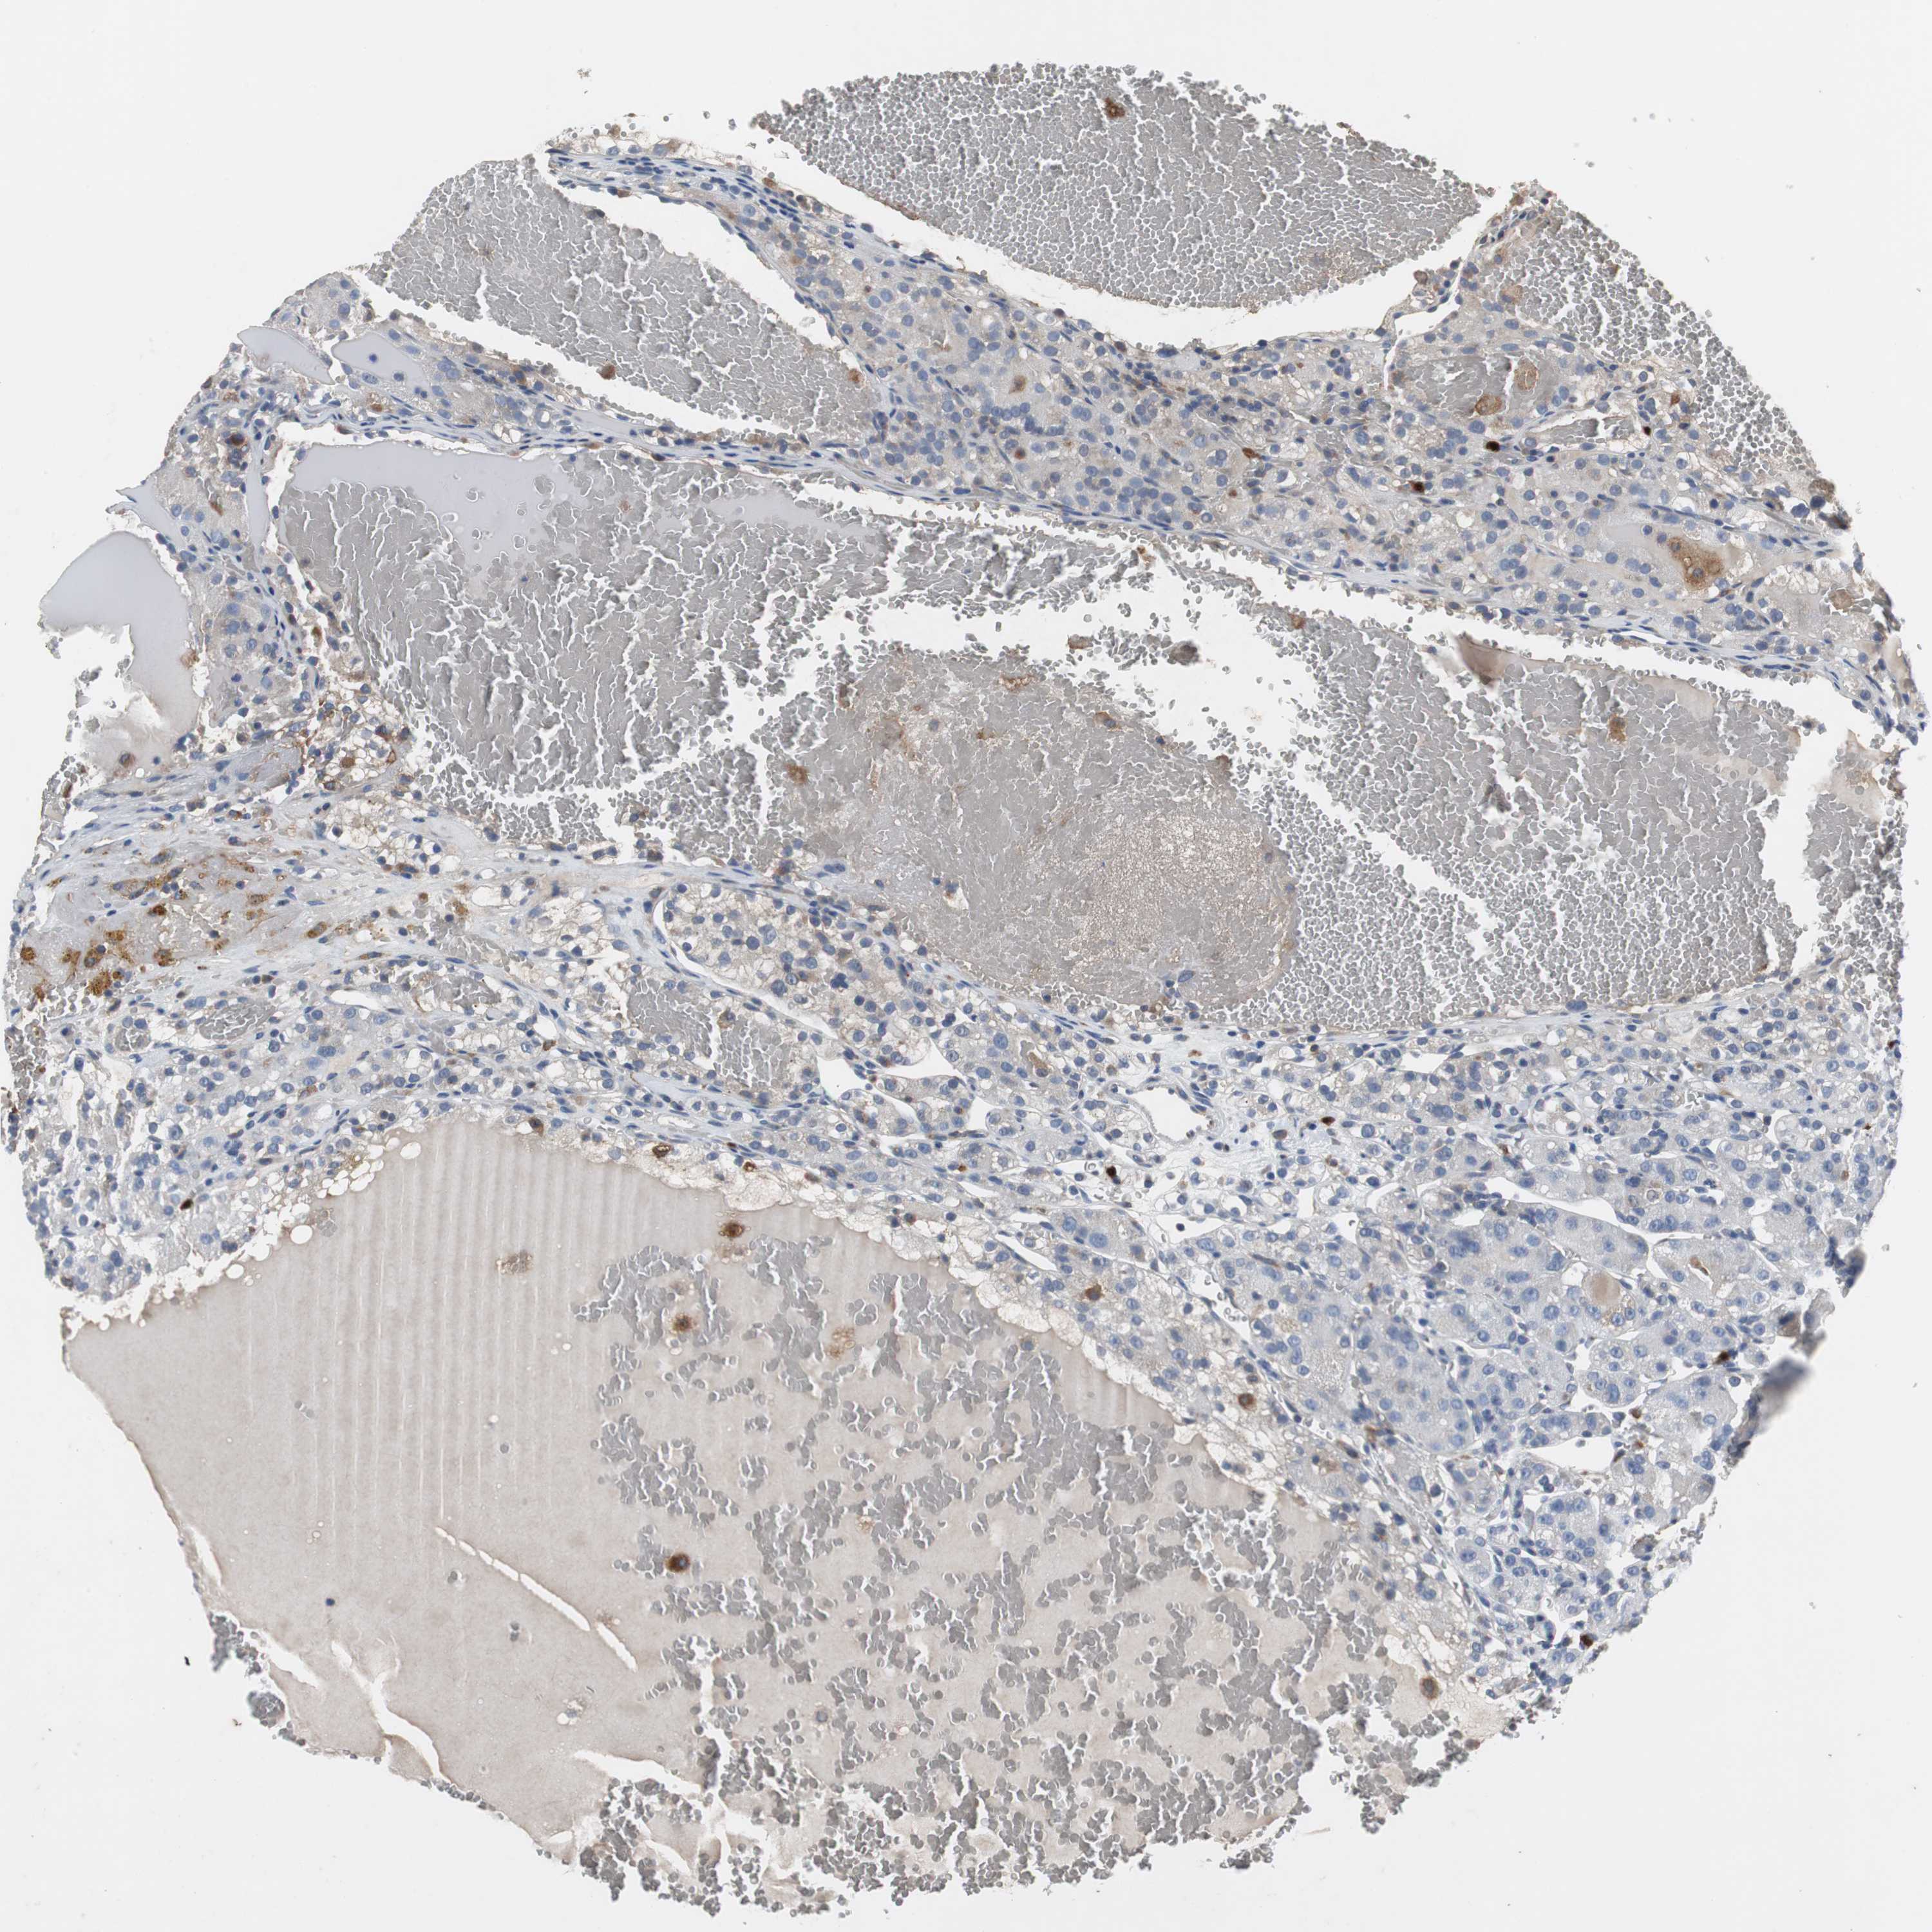

Average pTPM 0.3

Number of samples 100